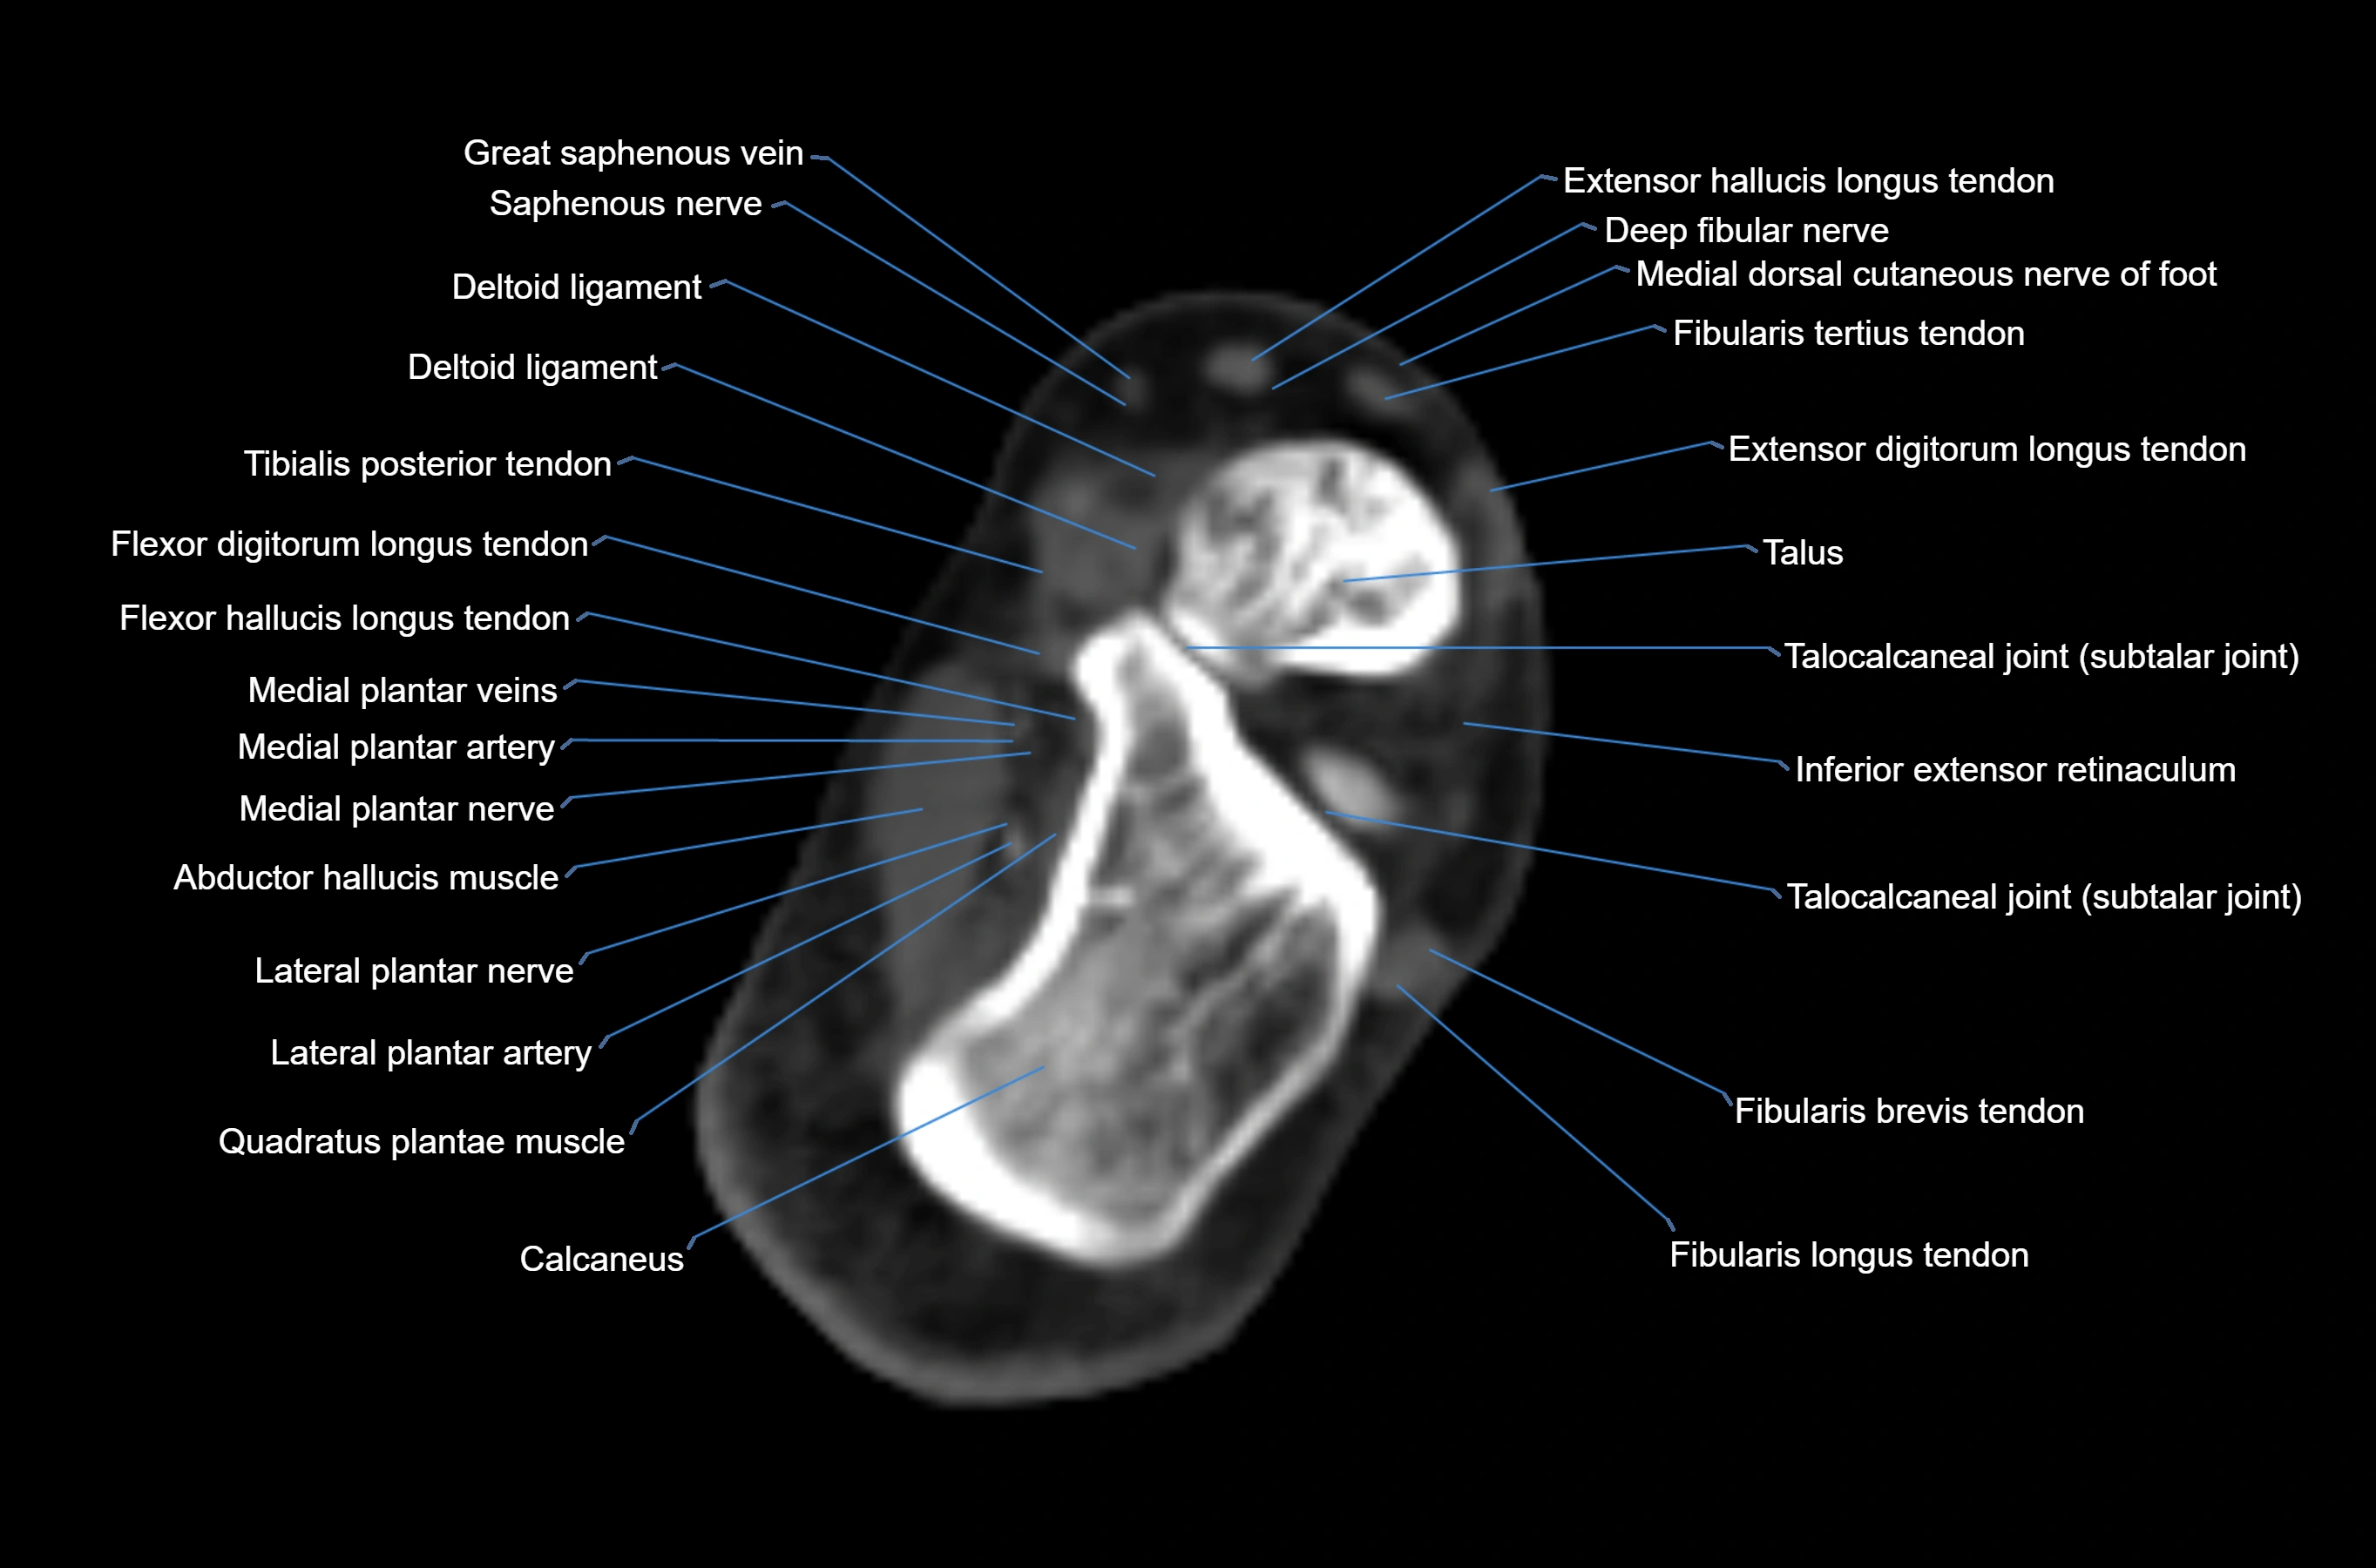

MRI image

CT image